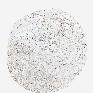

COLON ADENOCARCINOMA (VALIDATION) - Interactive survival scatter ploti

The Survival Scatter plot shows the clinical status (i.e. dead or alive) for all individuals in the patient cohort, based on the same data that underlies the corresponding Kaplan-Meier plots. Patients that are alive at last time for follow-up are shown in blue and patients who have died during the study are shown in red.

The x-axis shows the expression levels (FPKM) of the investigated gene in the tumor tissue at the time of diagnosis. The y-axis shows the follow-up time after diagnosis (years). Both axes are complimented with kernel density curves demonstrating the data density over the axes. The top density plot shows the expression levels (FPKM) distribution among dead (red) and alive patients (blue). The right density plot shows the data density of the survived years of dead patients with high and low expression levels respectively, stratified using the cutoff indicated by the vertical dashed line through the Survival Scatter plot. This cutoff is automatically defined based on the FPKM cutoff that minimizes the p-score. The cutoff can be changed by dragging the vertical line or by entering a cutoff value in the square labeled "Current cut-off".

Under the Survival Scatter plot the p-score landscape (black curve; left axis) is shown together with dead median separation (red curve; right axis). Dead median separation is the difference in median mRNA expression between patients who have died with high and low expression, respectively. It is calculated as follows: median FPKM expression of dead patients with high expression - median FPKM expression of dead patients with low expression. This is intended to aid the user in visually exploring custom cutoffs and the associated p-scores and dead median separation.

Individual patient data is displayed and can be filtered by clicking on one or more of the category buttons on the top of the page. Categories describing expression level and patient information include: high, low, alive, dead, female, male and tumor stages. The scale of the x-axis can be toggled between linear and log-scale by clicking on the "x log" button. Mouse-over function shows TCGA ID, patient information and mRNA expression (FPKM) for each patient.

& Survival analysisi

Kaplan-Meier plots summarize results from analysis of correlation between mRNA expression level and patient survival. Patients were divided based on level of expression into one of the two groups "low" (under cut off) or "high" (over cut off). X-axis shows time for survival (years) and y-axis shows the probability of survival, where 1.0 corresponds to 100 percent.

CDH6 is not prognostic in Colon Adenocarcinoma (validation)

Best expression cut offi

Based on the FPKM value of each gene, patients were classified into two groups and association between prognosis (survival) and gene expression (FPKM) was examined. The best expression cut-off refers the FPKM value that yields maximal difference with regard to survival between the two groups at the lowest log-rank P-value. Best expression cut-off was selected based on survival analysis .

When clicking on this number, the vertical dashed line indicating cut-off, the interactive survival plot, and the Kaplan-Meier curve will be adjusted to show results based on the best expression cut-off.

: 6.52

Median expressioni

Median expression refers to the median FPKM value calculated based on the gene expression (FPKM) data from all patients in this dataset. When clicking on this number, the vertical dashed line indicating cut-off, the interactive survival plot, and the Kaplan-Meier curve will be adjusted to show results based on the median expression.

: N/A

P scorei

Log-rank P value for Kaplan-Meier plot showing results from analysis of correlation between mRNA expression level and patient survival.

N/A

5-year survival highi

5-year survival for patients with higher expression than the expression cutoff.

For melanoma and glioma, 3-year survival is shown.

5-year survival lowi

5-year survival for patients with lower expression than the expression cutoff.

TCGA RNA samplesi

RNA-seq data is reported as average FPKM (number Fragments Per Kilobase of exon per Million reads), generated by the The Cancer Genome Atlas (TCGA) .

Normal distribution across the dataset is visualized with box plots, shown as median and 25th and 75th percentiles. Points are displayed as outliers if they are above or below 1.5 times the interquartile range. FPKM values of the individual samples are presented next to the box plot.

Average pTPM 5.4

Number of samples 486